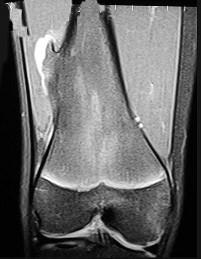

男,13岁,运动后膝痛,请结合影像图像,选择最可能的诊断()A.正常影像B.动脉瘤样骨囊肿C.骨软骨瘤D.成骨细胞瘤E.骨样骨瘤

问题 男,13岁,运动后膝痛,请结合影像图像,选择最可能的诊断()

选项 A.正常影像 B.动脉瘤样骨囊肿 C.骨软骨瘤 D.成骨细胞瘤 E.骨样骨瘤

答案 C